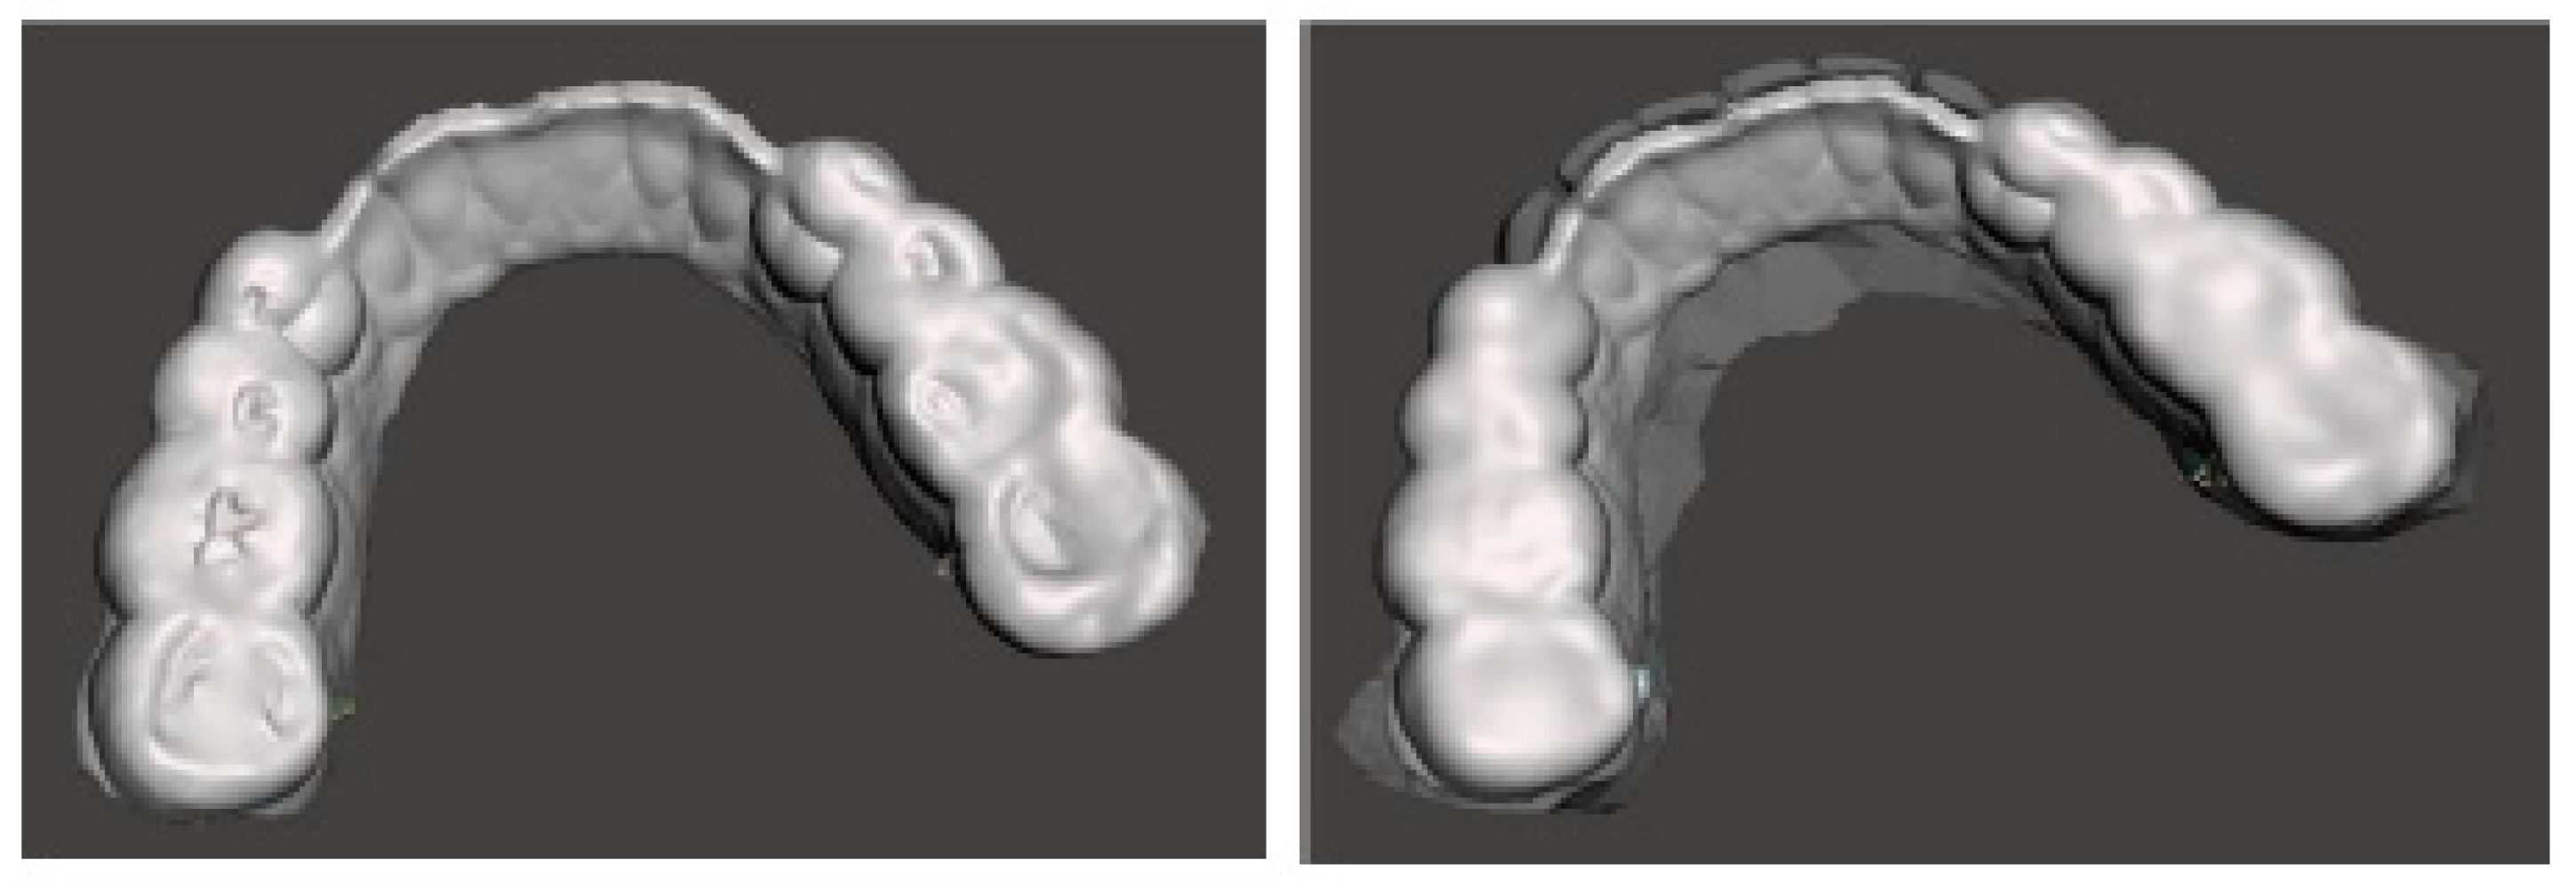

The present case is from a 45-year-old woman affected by TMDs, based on DC/TMD [10]. In her medical history, the patient reported that she was aware of suffering for years from awake bruxism, which manifested itself above all during moments of concentration and intellectual work, associated with headache in the area of the temples, with pain in the masseter muscles and, occasionally, with bilateral swelling of the temple areas. The diagnosis was, therefore, myofascial pain of the masseter muscles with associated headache, right and left disc displacement without reduction, and a slightly reduced opening path [11,12]. Intraoral clinical examination evidenced alteration of the occlusal plane, with numerous wear facets and completely abraded posterior teeth with uncovering of the dentin (Figure 2).

Figure 2. Occlusal view (STL files).